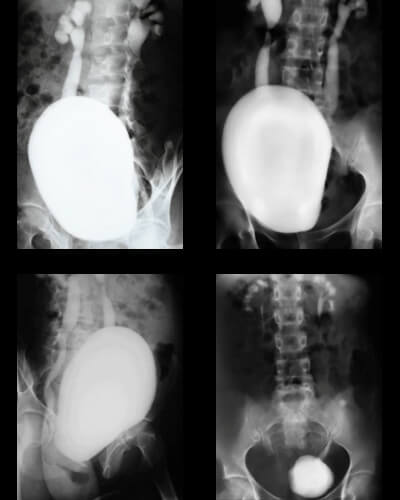

A Uretrocistografia é um exame radiológico que estuda a morfologia e a função da uretra e da bexiga. É frequentemente utilizado para diagnosticar refluxos vesicoureterais, estenoses (estreitamentos) e outras malformações urinárias.

Qualidade Clinimagem: Realizamos o procedimento seguindo rigorosos protocolos de higiene e segurança, garantindo imagens nítidas para um diagnóstico preciso tanto em adultos quanto em crianças.